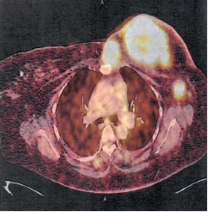

[68Ga] Ga-FAPI PET-CT scan was then performed and the interpretation with comparison to baseline [18F] F-FDG PET -CT scan was done by the same user. The study demonstrated abnormal FAPI uptake in the known left breast tumor and one ipsilateral satellite small chest lesion, both with central areas of no uptake in keeping with necrotic tissue. On low dose CT, the breast tumour measured 5.1 x 5.8 cm (AP X TV) and a satellite mass abutting the sternum measured 2.1 x3 cm (AP x TV) with no underlying bone changes (Figure 3 & 4).

Figure 4: FAPI PET-CT fusion projection showed intense FAPI uptake in the left breast and a satellite mass, both with central necrosis. Intense FAPI uptake was also seen in the retropectoral lymph node located just below the left breast mass.

There was also a low-grade uptake involving retropectoral node. The left axillary lymph nodes also demonstrated low grade uptake with fat hila on CT, these were considered benign. On dedicated lung window CT, lung fields were clear (Figure 5).